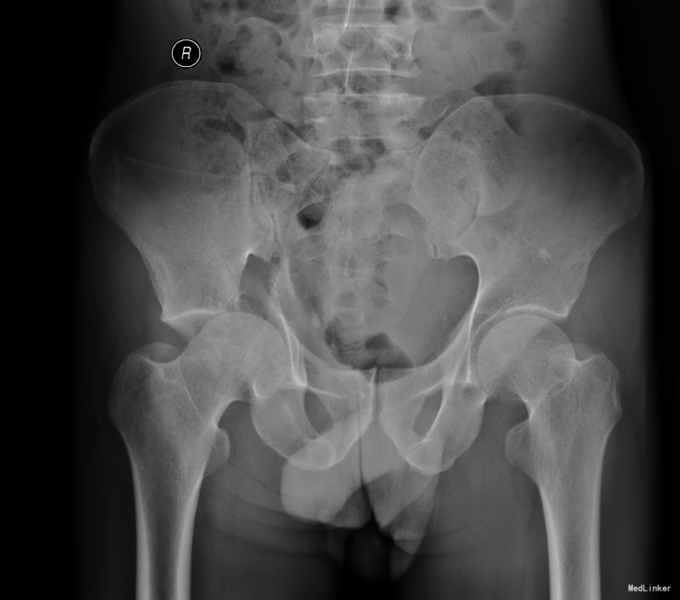

患者于2015年6月10日因车祸摔伤右侧髋关节,出现右髋部疼痛及活动受限。疼痛于活动后加重,休息可稍缓解。后就诊于营口市中心医院行骨盆三维CT示“右髋臼粉碎性骨折”,建议手术治疗,给予胫骨结节骨牵引术,患者于6月17日收入我院运动关节科病房,于6月19日转入我科。

专科查体:患者平车入病房,有大腿内收畸形,右髋部疼痛,压痛(+),左腹股沟处疼痛,自述左下肢稍麻木,右下肢感觉无异常,双下肢活动可,双侧足背动脉可触及。